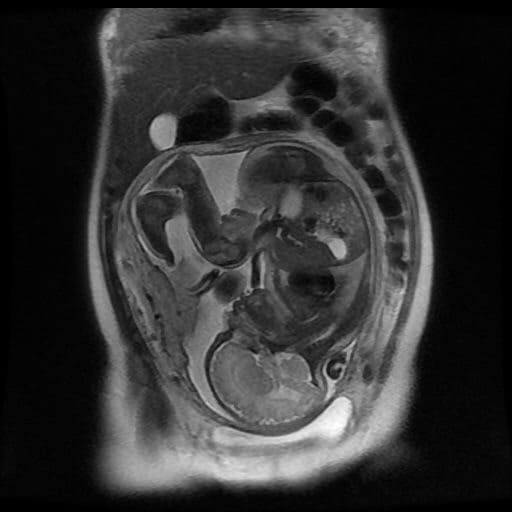

Магнитно-резонансная томография – современный и высокоэффективный инструмент диагностики, с помощью которого врач может не только исследовать структуру внутренних органов плода, но также и изучить их функциональность, выявить пороки развития и оказать влияние на протекание беременности, своевременно начать лечение. Первый триместр – время закладки органов будущего ребенка, поэтому МРТ плода в основном назначается врачом после трех месяцев беременности.

МРТ позволяет детально оценить развитие головного мозга (пороки, кровоизлияния), позвоночника, органов грудной и брюшной полости, лица, а также выявить патологии плаценты и пуповины.